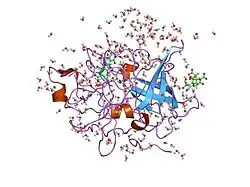

Urokinase is a 411-residue protein, consisting of three domains: the serine protease domain (consisting of residues 159–411), the kringle domain (consisting of residues 50-131), and the EGF-like domain (consisting of residues 1-49). The kringle domain and the serine protease domain are connected by an interdomain linker or connecting peptide (consisting of residues 132–158). Urokinase is synthesized as a zymogen form (prourokinase or single-chain urokinase), and is activated by proteolytic cleavage between Lys158 and Ile159. The two resulting chains are kept together by a disulfide bond between Cys148 and Cys279.[9]